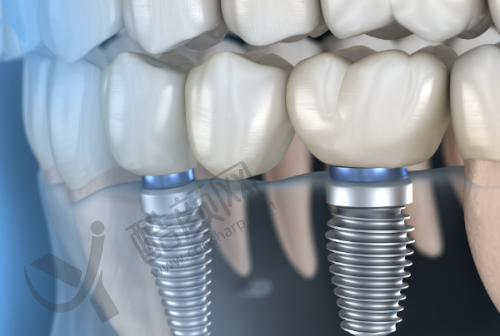

史衡涛医生在种植牙领域有着深厚的造诣,其技术水平非常可靠。他擅长全口种植牙、半口种植牙、单颗种植、多颗种植以及即刻种植牙等多种种植技术。在临床实践中,面对不同患者复杂的口腔状况,他都能精细分析并制定出更适合的种植方案。

他致力于为患者提供无疼痛的种植牙体验,采用微创技术来减少手术带来的不适。许多患者反映,在他的治疗下,不仅手术过程顺利,而且修养期也相对较短,极大地减轻了他们的痛苦。他还积极应用临床新技术,尤其是在微创保护性修复方面,他的研究成果得到了同行的高度评价。